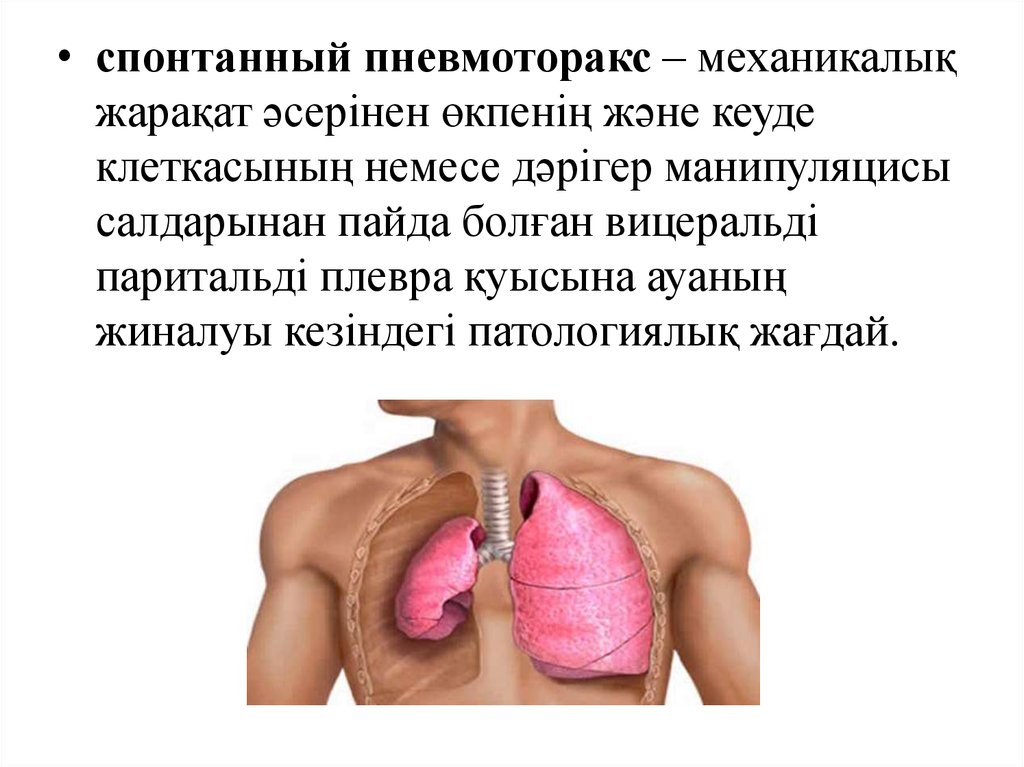

Схемы дыхания: Пневмоторакс на изображениях